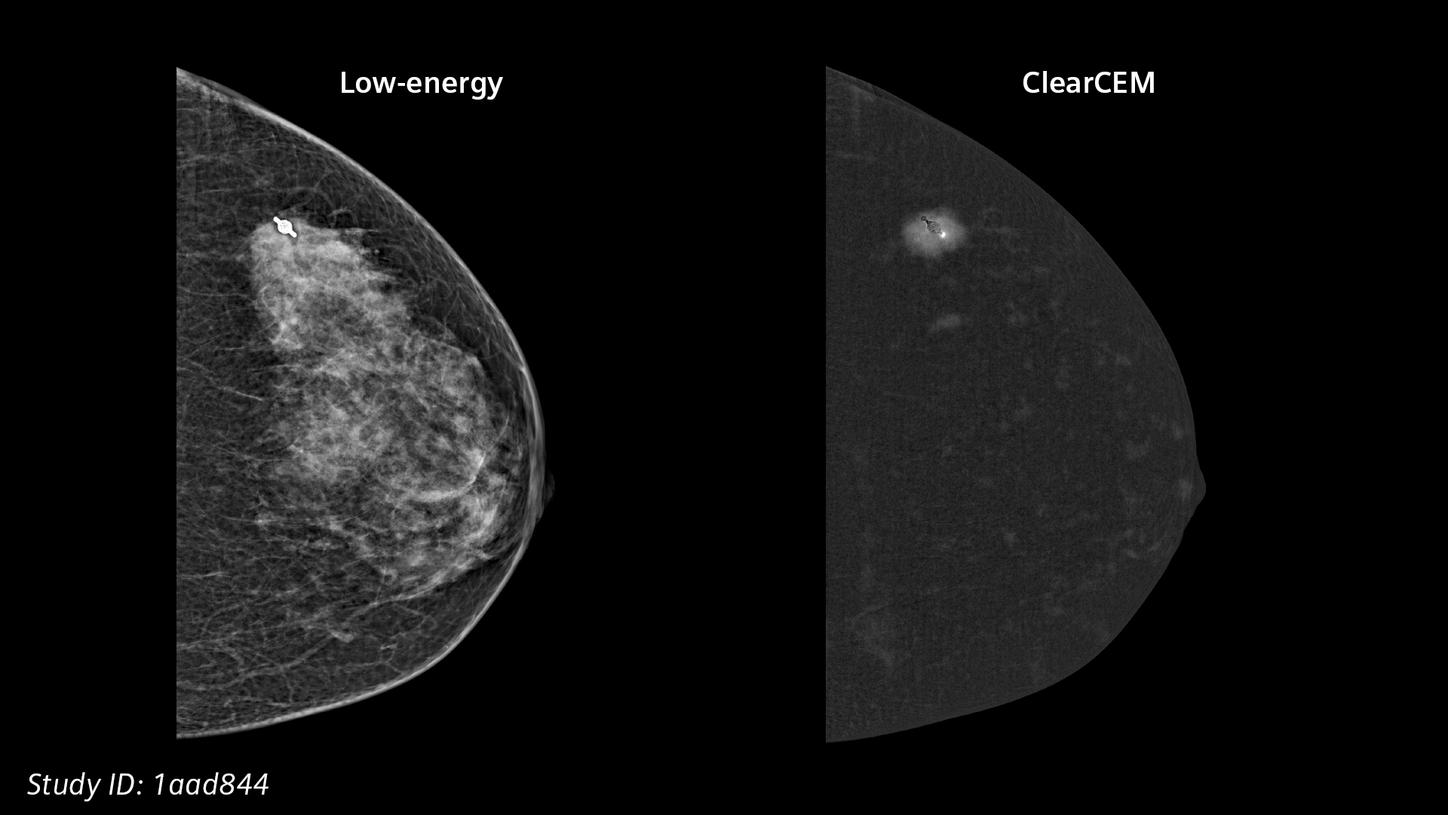

Our new recombination algorithm lifts CEM (contrast-enhanced mammography) breast imaging to a higher, brilliant level: with outstanding image quality, we are setting a new benchmark for accuracy and diagnostic certainty, bringing mammography closer to MRI.

ClearCEMA new era in contrast-enhanced mammography